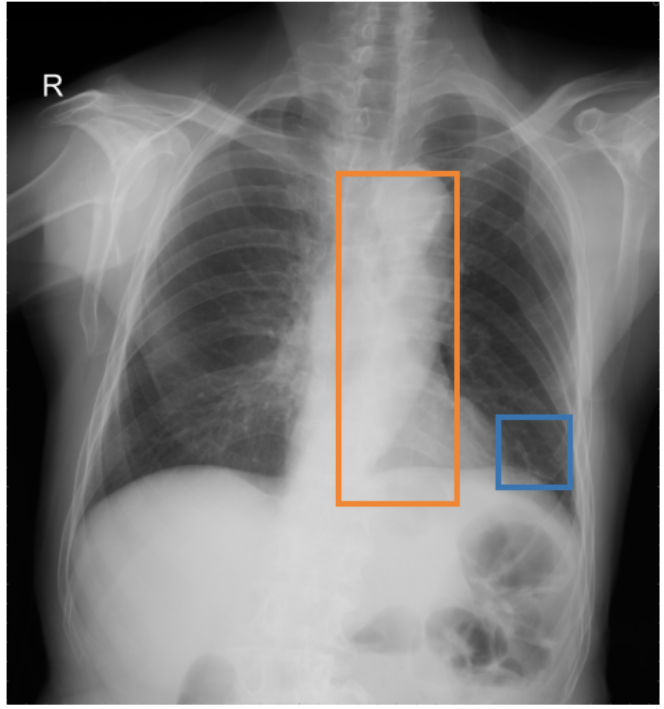

To address these drawbacks, state-of-the-art models such as MAIRA-2 [3] explicitly incorporate grounded report generation to better align local visual evidence with the textual findings. For example, MAIRA-2 is trained on a diverse set of localization-based tasks, including phrase grounding and grounded report generation. However, as shown in Figure 1, current models often exhibit a bias in which the target visual regions become overly associated with abnormal findings, leading to false positives in medical reports.

As shown in Table 1, our data composition reflects this imbalance: over 12.9M instances from Chest ImaGenome dominate the much smaller MS-CXR (815 PG instances) and PadChest-GR (12k instances) datasets. Beyond the imbalance between datasets, each dataset also exhibits substantial intra-dataset class imbalance. For example, anatomical regions in AGRG and semantic categories in PG are unevenly represented, leading the model to overfit frequent regions, neglect rare but clinically important ones, and hallucinate findings (Figure 1). Our curriculum framework addresses both sources of imbalance.

While MAIRA-2 exhibits a slightly lower hallucination rate for a few anatomies (e.g., ‘Cardiac Silhouette’), CURE consistently achieves a significantly lower contradiction rate and higher entailment rate across almost all categories. This improved performance likely stems from a key difference in the training data composition. Standard phrase grounding, used by MAIRA-2, is inherently biased towards abnormal findings. In contrast, our AGRG formulation exposes the model to both normal and abnormal descriptions for each anatomical region, leading to a more balanced and reliable generative process that mitigates the tendency to hallucinate abnormalities.